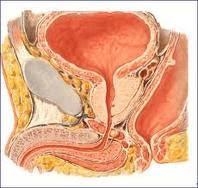

Investigadores de la Universidad de Wake Forest, en Winston-Salem, Carolina del Norte, coordinados por Yuanyuan Zhang, han desarrollado tejido similar a uretra mediante el crecimient0 de células madre extraídas de la orina de cuatro voluntarios sanos a partir de tejido intestinal de cerdo. Para llevar a cabo este trabajo, cuyas conclusiones se publican en la revista Biomaterials , el equipo de científicos ha convertido por primera vez células madre de la orina en células uroteliales y células musculares lisas -líneas celulares vitales para generar uréteres y uretras-.Después, Zhang despojó todas las células del cerdo de las capas del tejido intestinal, dejando únicamente el armazón proteico del colágeno inerte subyacente. El investigador cubrió este armazón con dos tipos de células. Dos semanas más tarde las células depositadas formaron capas sobre los andamios que se asemejan a las uretras o uréteres. En otro experimento, las mismas estructuras desarrolladas tras los armazones "sembrados" habían sido implantados en ratones que carecían de sistema inmune, probando que las células pueden sobrevivir y crecer en animales vivos. Zhang planea llevar a cabo más investigaciones en un mayor número de animales y, de manera eventual, en humanos.

Investigadores de la Universidad de Wake Forest, en Winston-Salem, Carolina del Norte, coordinados por Yuanyuan Zhang, han desarrollado tejido similar a uretra mediante el crecimient0 de células madre extraídas de la orina de cuatro voluntarios sanos a partir de tejido intestinal de cerdo. Para llevar a cabo este trabajo, cuyas conclusiones se publican en la revista Biomaterials , el equipo de científicos ha convertido por primera vez células madre de la orina en células uroteliales y células musculares lisas -líneas celulares vitales para generar uréteres y uretras-.Después, Zhang despojó todas las células del cerdo de las capas del tejido intestinal, dejando únicamente el armazón proteico del colágeno inerte subyacente. El investigador cubrió este armazón con dos tipos de células. Dos semanas más tarde las células depositadas formaron capas sobre los andamios que se asemejan a las uretras o uréteres. En otro experimento, las mismas estructuras desarrolladas tras los armazones "sembrados" habían sido implantados en ratones que carecían de sistema inmune, probando que las células pueden sobrevivir y crecer en animales vivos. Zhang planea llevar a cabo más investigaciones en un mayor número de animales y, de manera eventual, en humanos.

Investigadores de la Universidad de Wake Forest, en Winston-Salem, Carolina del Norte, coordinados por Yuanyuan Zhang, han desarrollado tejido similar a uretra mediante el crecimient0 de células madre extraídas de la orina de cuatro voluntarios sanos a partir de tejido intestinal de cerdo. Para llevar a cabo este trabajo, cuyas conclusiones se publican en la revista Biomaterials , el equipo de científicos ha convertido por primera vez células madre de la orina en células uroteliales y células musculares lisas -líneas celulares vitales para generar uréteres y uretras-.Después, Zhang despojó todas las células del cerdo de las capas del tejido intestinal, dejando únicamente el armazón proteico del colágeno inerte subyacente. El investigador cubrió este armazón con dos tipos de células. Dos semanas más tarde las células depositadas formaron capas sobre los andamios que se asemejan a las uretras o uréteres. En otro experimento, las mismas estructuras desarrolladas tras los armazones "sembrados" habían sido implantados en ratones que carecían de sistema inmune, probando que las células pueden sobrevivir y crecer en animales vivos. Zhang planea llevar a cabo más investigaciones en un mayor número de animales y, de manera eventual, en humanos.

Investigadores de la Universidad de Wake Forest, en Winston-Salem, Carolina del Norte, coordinados por Yuanyuan Zhang, han desarrollado tejido similar a uretra mediante el crecimient0 de células madre extraídas de la orina de cuatro voluntarios sanos a partir de tejido intestinal de cerdo. Para llevar a cabo este trabajo, cuyas conclusiones se publican en la revista Biomaterials , el equipo de científicos ha convertido por primera vez células madre de la orina en células uroteliales y células musculares lisas -líneas celulares vitales para generar uréteres y uretras-.Después, Zhang despojó todas las células del cerdo de las capas del tejido intestinal, dejando únicamente el armazón proteico del colágeno inerte subyacente. El investigador cubrió este armazón con dos tipos de células. Dos semanas más tarde las células depositadas formaron capas sobre los andamios que se asemejan a las uretras o uréteres. En otro experimento, las mismas estructuras desarrolladas tras los armazones "sembrados" habían sido implantados en ratones que carecían de sistema inmune, probando que las células pueden sobrevivir y crecer en animales vivos. Zhang planea llevar a cabo más investigaciones en un mayor número de animales y, de manera eventual, en humanos.